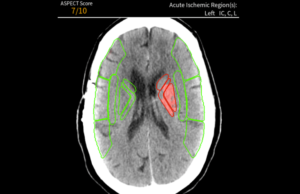

Avicenna.AI receives CE Mark for AI tool to assess stroke severity

Medical imaging AI specialist Avicenna.AI has received CE mark certification for its CINA ASPECTS AI tool for stroke severity assessment. CINA ASPECTS automatically processes...